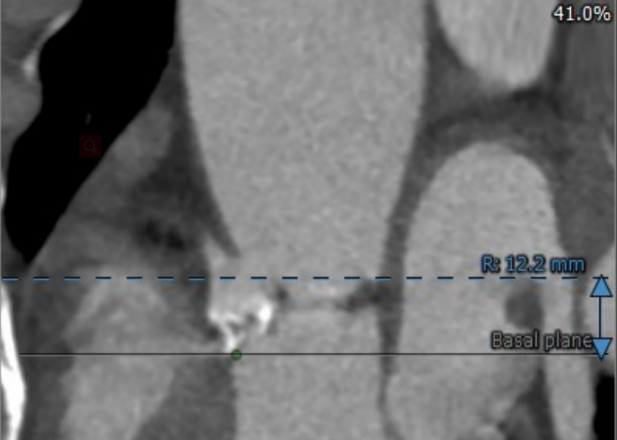

患者男性,70岁,重度钙化型主动脉瓣狭窄,STS评分8.6%,常规外科手术高风险。术前心脏超声提示主动脉瓣严重增厚钙化,峰值流速5.4m/s,平均跨瓣压差82mmHg。CT评估结果显示主动脉瓣重度钙化,瓣环平均直径23.9mm,瓣环面积448.4mm²。左冠脉开口高度8.5mm,右冠脉开口高度12.2mm。该患者左、右冠状动脉开口高度低,左冠瓣叶较长伴钙化,且瓦氏窦较小,窦管交界处高度低,冠状动脉阻塞风险高,手术操作复杂。

右冠状动脉高度